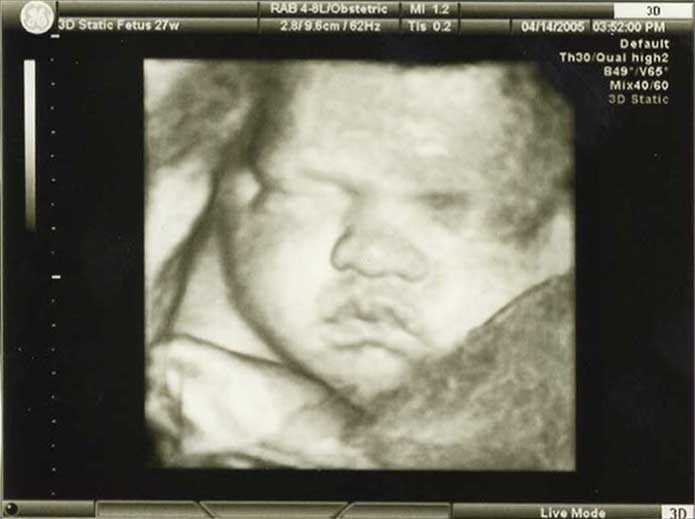

3D/4D HD LIVE

Στο ιατρείο μας προσφέρουμε υψηλής ευκρίνειας 3D και 4D τεχνολογία απεικόνισης του εμβρύου. Η τεχνολογία αυτή αποτελεί ένα ακόμα σημαντικό διαγνωστικό όπλο στη φαρέτρα του προγεννητικού ελέγχου, ενώ ταυτόχρονα ενισχύει την ανάπτυξη του δεσμού ανάμεσα στους μελλοντικούς γονείς και το μωρό τους.